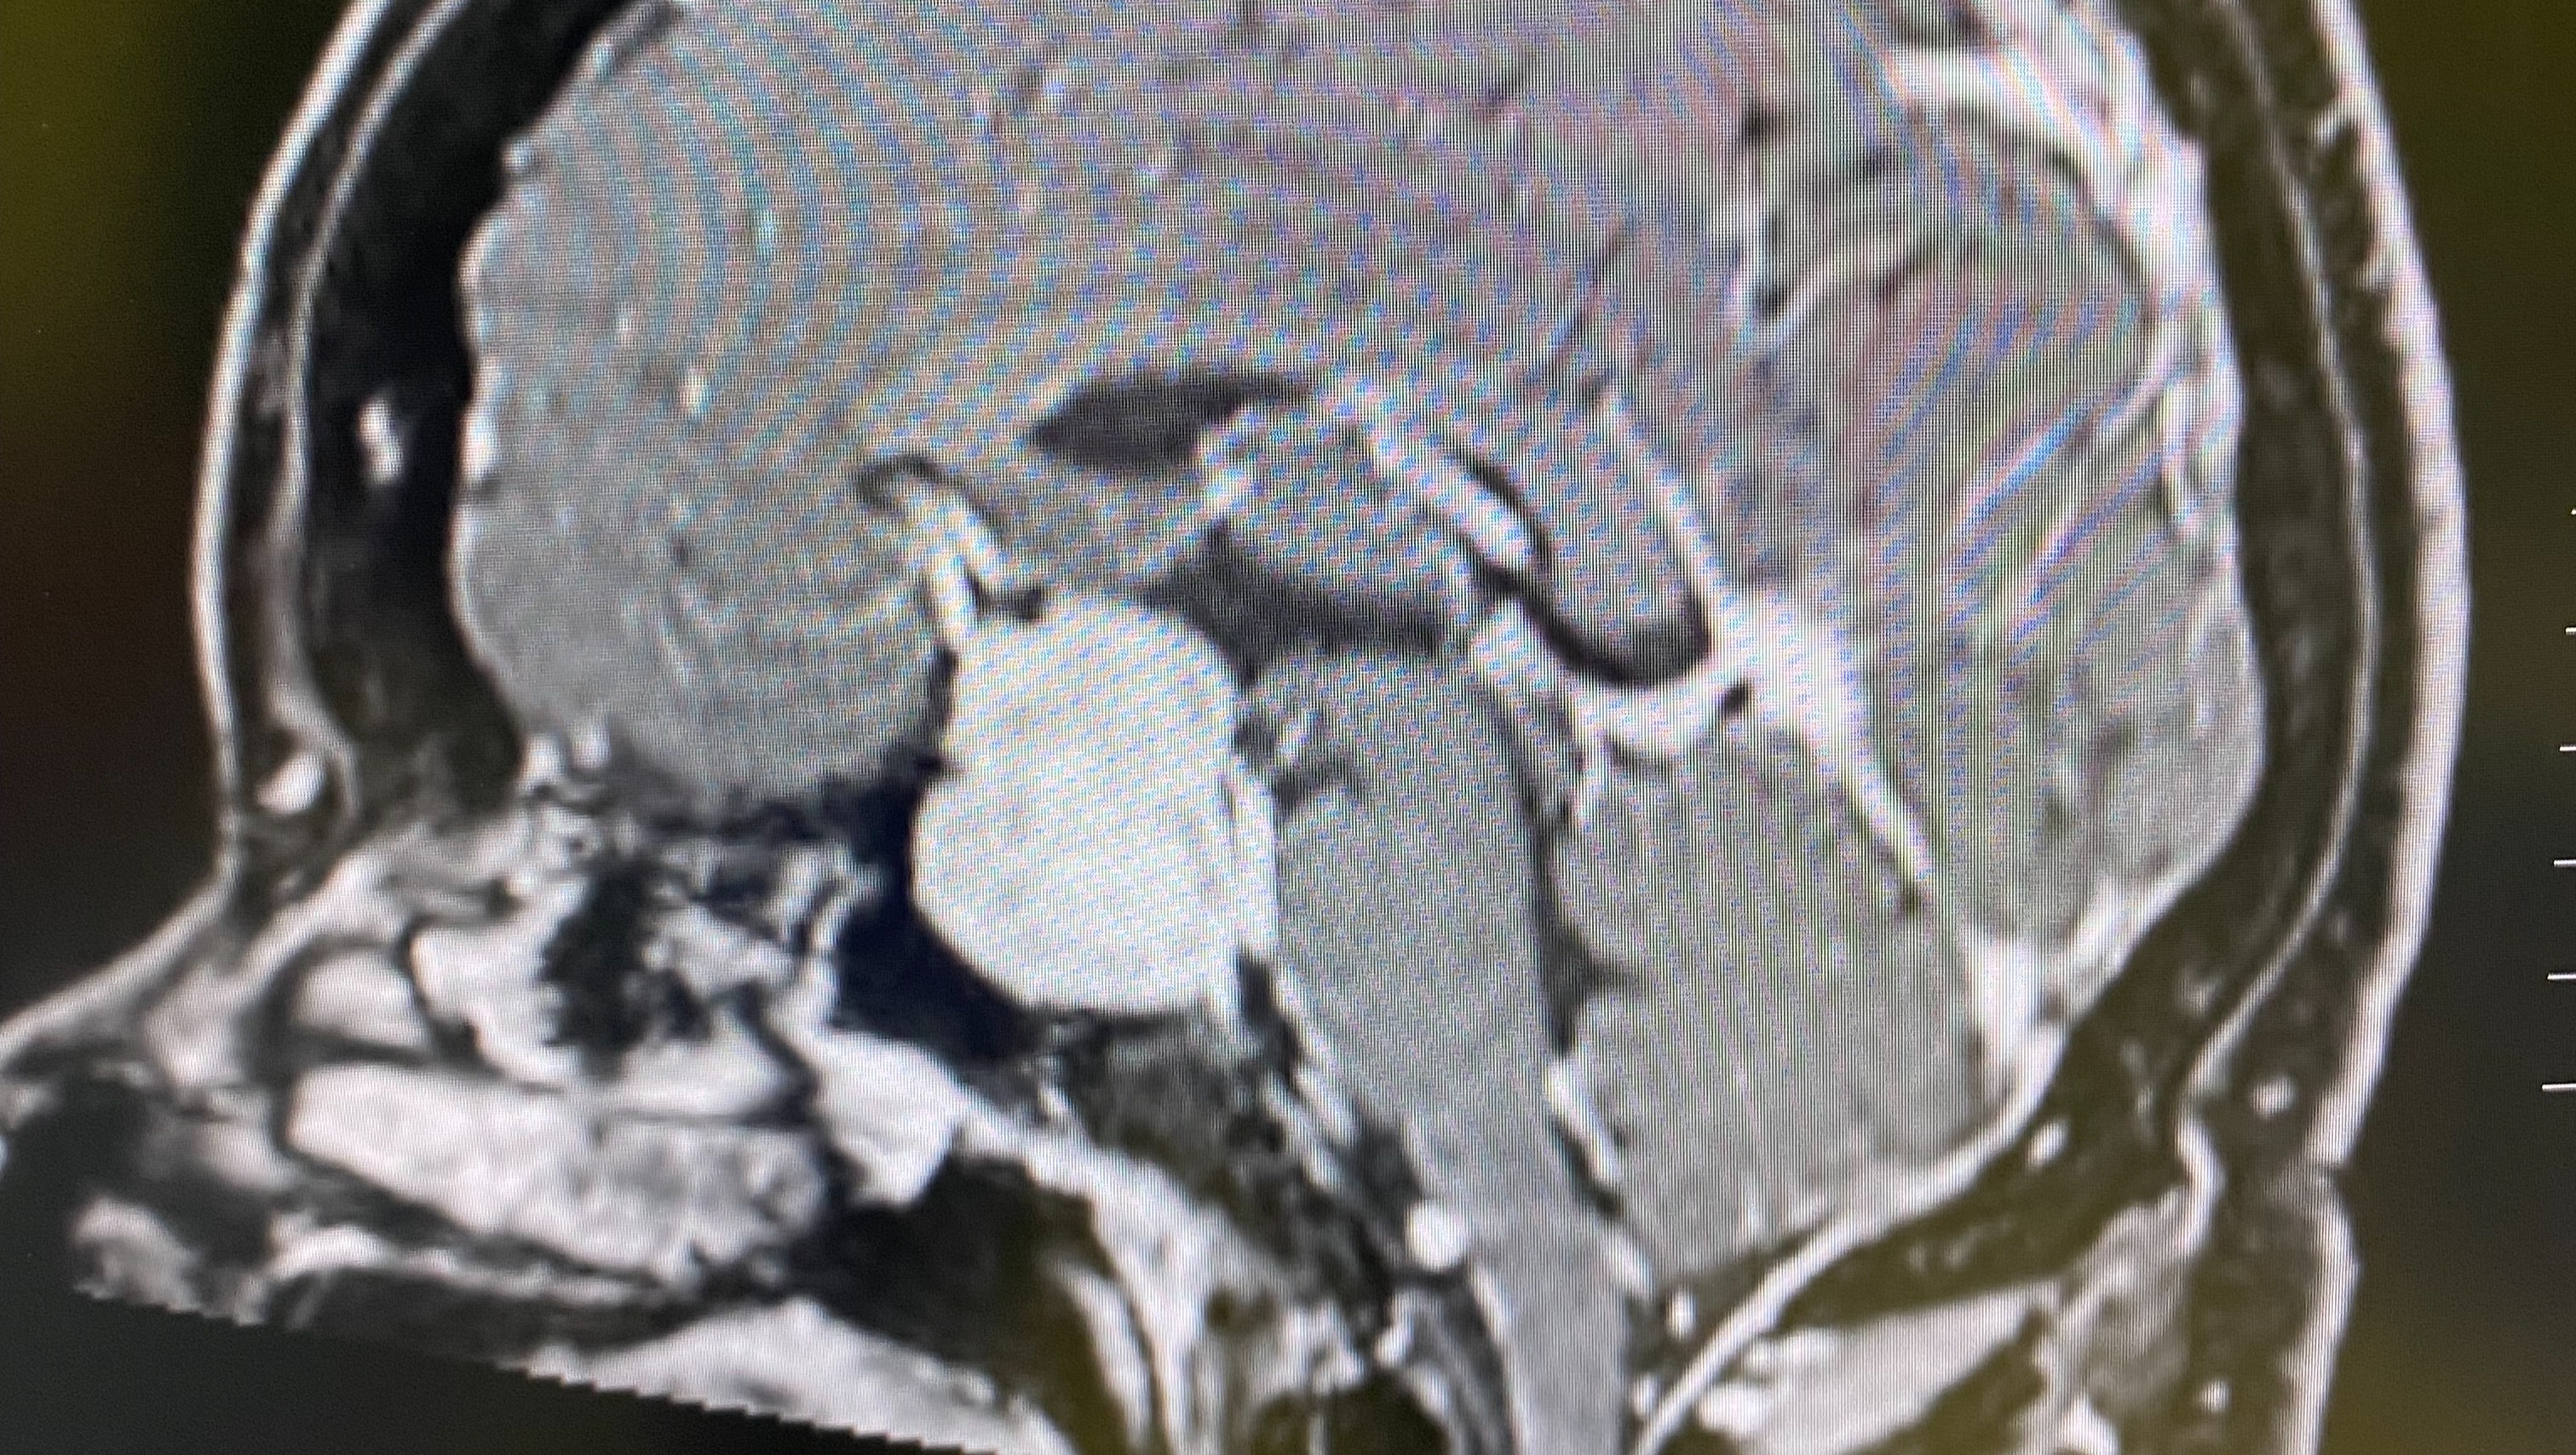

Dear friends, family, and unknown Angels, My name is Shawn Key, and I’m reaching out to share my journey as I battle a brain tumor diagnosed this past December. This fight has not only taken a toll on my physical health but has also led me to make difficult decisions that have changed my life. In November 2025, I made the heart-wrenching choice to shut down my owner operated pest control business. The symptoms I was experiencing became overwhelming. I faced blindness in my left eye, which made it impossible to continue my work, along with dizziness, fatigue, anxiety, and muscle and bone weakness. Simple tasks became monumental challenges, and daily activities that I once took for granted have become daunting. These challenges have not only impacted my ability to work but have also led to significant medical and transportation expenses. That means more than just a major medical procedure—it also means dealing with scans, medications, travel to specialists, and many missed days of work. I will require regular treatments and appointments. Despite these hurdles, I am determined to fight and keep faith in God. However, the financial burden is becoming increasingly difficult to manage. I’m asking for your support to help cover medical expenses, treatments, therapies, medications, transportation to and from appointments, and daily living expenses. With my business closed, I’ve lost a significant source of income. Your support will help cover medical expenses, medication, follow-up tests and treatment expenses, lost income during recovery, rent, utilities, food delivery and groceries, aftercare, travel to post-surgery appointments, and physical therapy. Everyday expenses while recuperating add up quickly. I realize times are hard—no amount is too small, and I certainly welcome your prayers. You’re not just helping me financially—you’re helping me alleviate stress and reminding me that I am not in this fight alone. If you are unable to contribute financially, sharing this campaign with your network would mean the world to me. Your support, whether through donations or sharing my story, is greatly appreciated. Thank you for taking the time to read my story and for considering helping me in this fight. With love and gratitude, Shawn Key